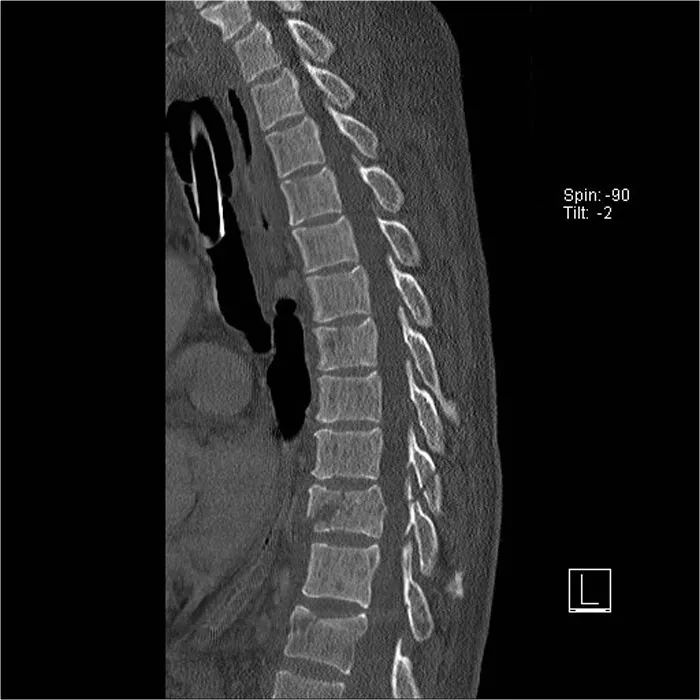

CT矢状位重建图像也显示皮质破裂。注意,在2.5mm的轴位片上,你可能会错过这些骨折,你得看看薄层才能发现这样微妙的骨折。如下图